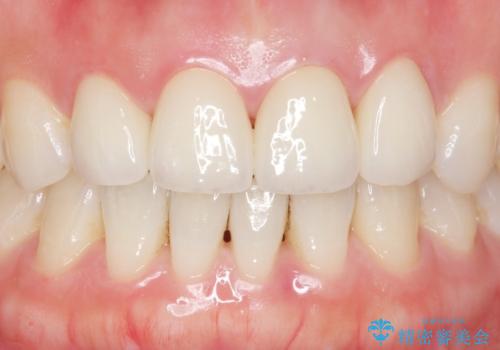

自然な仕上がりに大変喜んで頂けました。

単冠かつ適合の良いクラウンにより清掃性が良くなり、歯茎の腫れ・出血もなくなりました。

天然歯と見紛うほど自然なセラミッククラウンは、熟練した技工士さんの技術の賜物です。

クラウンの種類:ジルコニアオールセラミッククラウン エクセレント